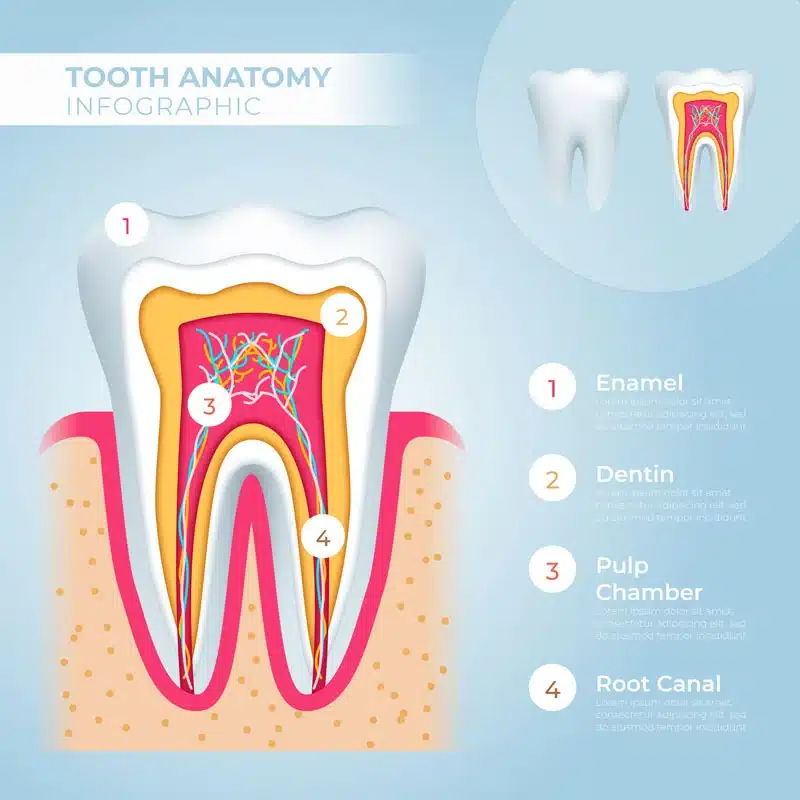

ریشه دندان

هنگامی که ریشه دندان میمیرد، ناراحتی اغلب از بین میرود. در این صورت، برای جلوگیری از گسترش عفونت به یک endo فوری نیاز دارید. هر چه مدت زمان عفونت طولانی تر باشد، احتمال اینکه نیاز به کشیدن دندان داشته باشید بیشتر است.

عفونت در پالپ دندان شما فقط با عصب کشی قابل درمان است و به خودی خود از بین نمی رود. کاهش درد ناشی از دندان درد به معنای رفع مشکل نیست. این در واقع نشان میدهد که عفونت بدتر شده و اعصاب ریشه دندان شما را از بین برده است.

آنتی بیوتیک نمیتوانند عفونت داخل دندان را درمان کنند. این به این دلیل است که داروهای آنتی بیوتیک نمی توانند به طور موثری از طریق جریان خون به پالپ دندان برسند. تنها راه برای از بین بردن عفونت استفاده از endo است.